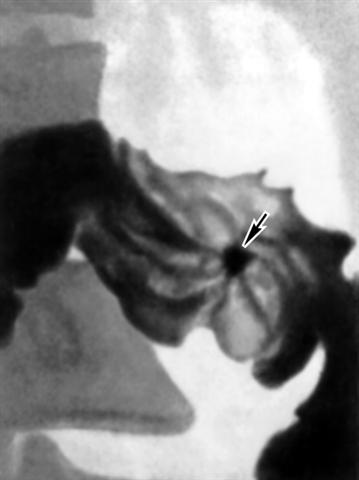

Рис. 1б). Прицельные рентгенограммы (в разных проекциях) луковицы двенадцатиперстной кишки при язвенной болезни: ниша рельефа, или фасная ниша (указана стрелкой), с конвергенцией к ней складок слизистой оболочки.